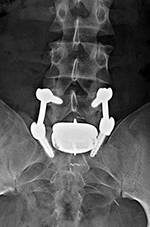

Lumbar spine bony disk strut, pedicle screws, and pedicle rods (AP view) |

20 year-old woman with L1 vertebral body compression fracture treated with T12-L2 posterior spinal fusion using pedicle screws at T12 and L2 with connecting rods on each side. |